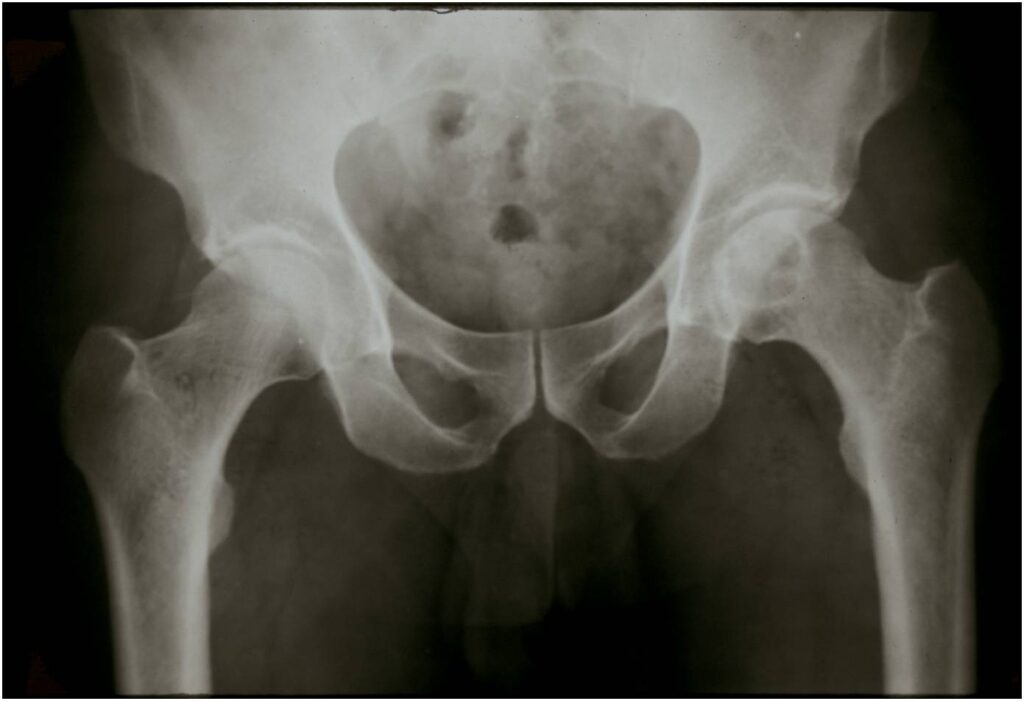

Sites:

- Epiphyses of long bones

- Most commonly proximal femur, proximal humerus, distal femur, proximal tibia

Radiographic Presentation

- Usually osteolytic, expansile lesion

- May be focally calcified

- Often a sharp interface between tumor and surrounding bone

- Sclerotic rim is uncommon

- Overlying cortex is usually thin, but intact